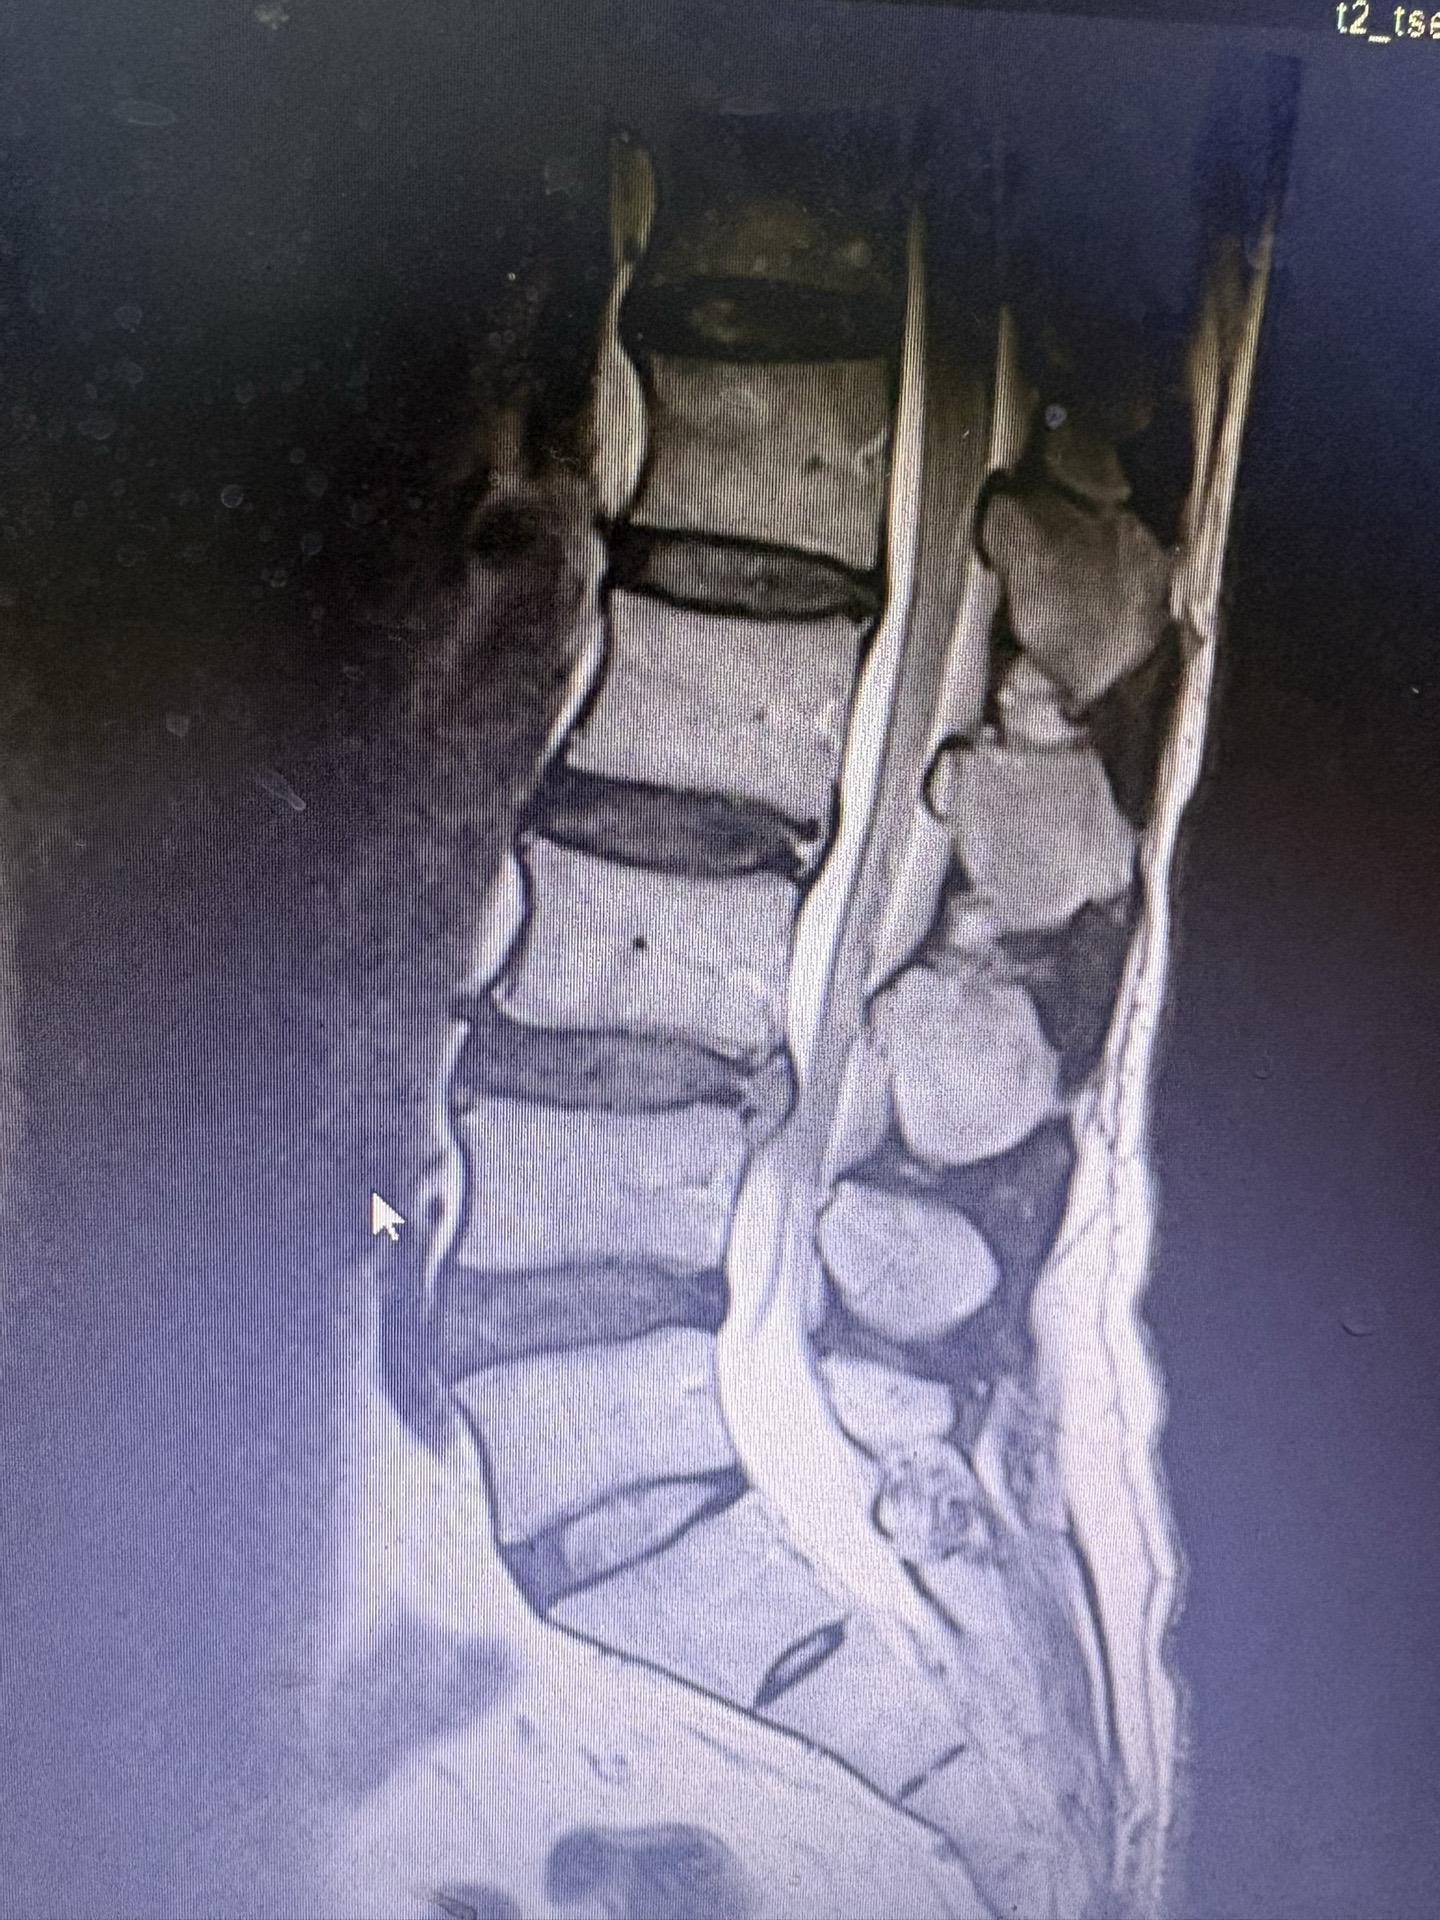

前段时间发现一例椎间盘突出病人保守治疗突出自行吸收,最近又发现一例治疗半年椎间盘突出已自行吸收,证明这不是个例。有部分人确实可以自行吸收,人的人体是很神奇的